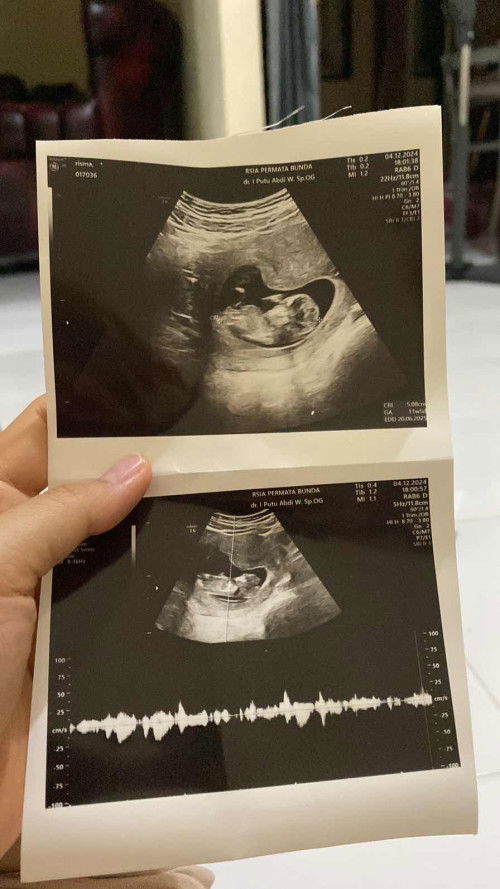

Bun aku mau berbagi pengalaman . Kemarin di usia janin ku 7 minggu . Aku keluar flek 2 hari 🥲. Terus aku usg ke dokter baru ada kantung kehamilan . Sedangkan normalnya katanya harus nya udah ada bakal janin. Al hasil aku di suruh usg 1 bulan lagi. Selama satu bulan itu aku drop banget. Jadi malas makan apapun karna bawaan aku juga gabisa nyium bau bawang. Aku cuman konsumsi asam folat (blackmories) , kalsium, sama d3 , dan susu manis indomilk kids karna cuman susu itu yang menurutku enak😆 . Udah satu bulan kemudian di usia kandungan ku 11 minggu usg lagi dan janin aku udah ada kata dokter nya janin ku sehat dan gede . Aktif banget lagi ya Allah aku bersyukur banget. Ada yang sama ga sih sama pengalamankuu ??